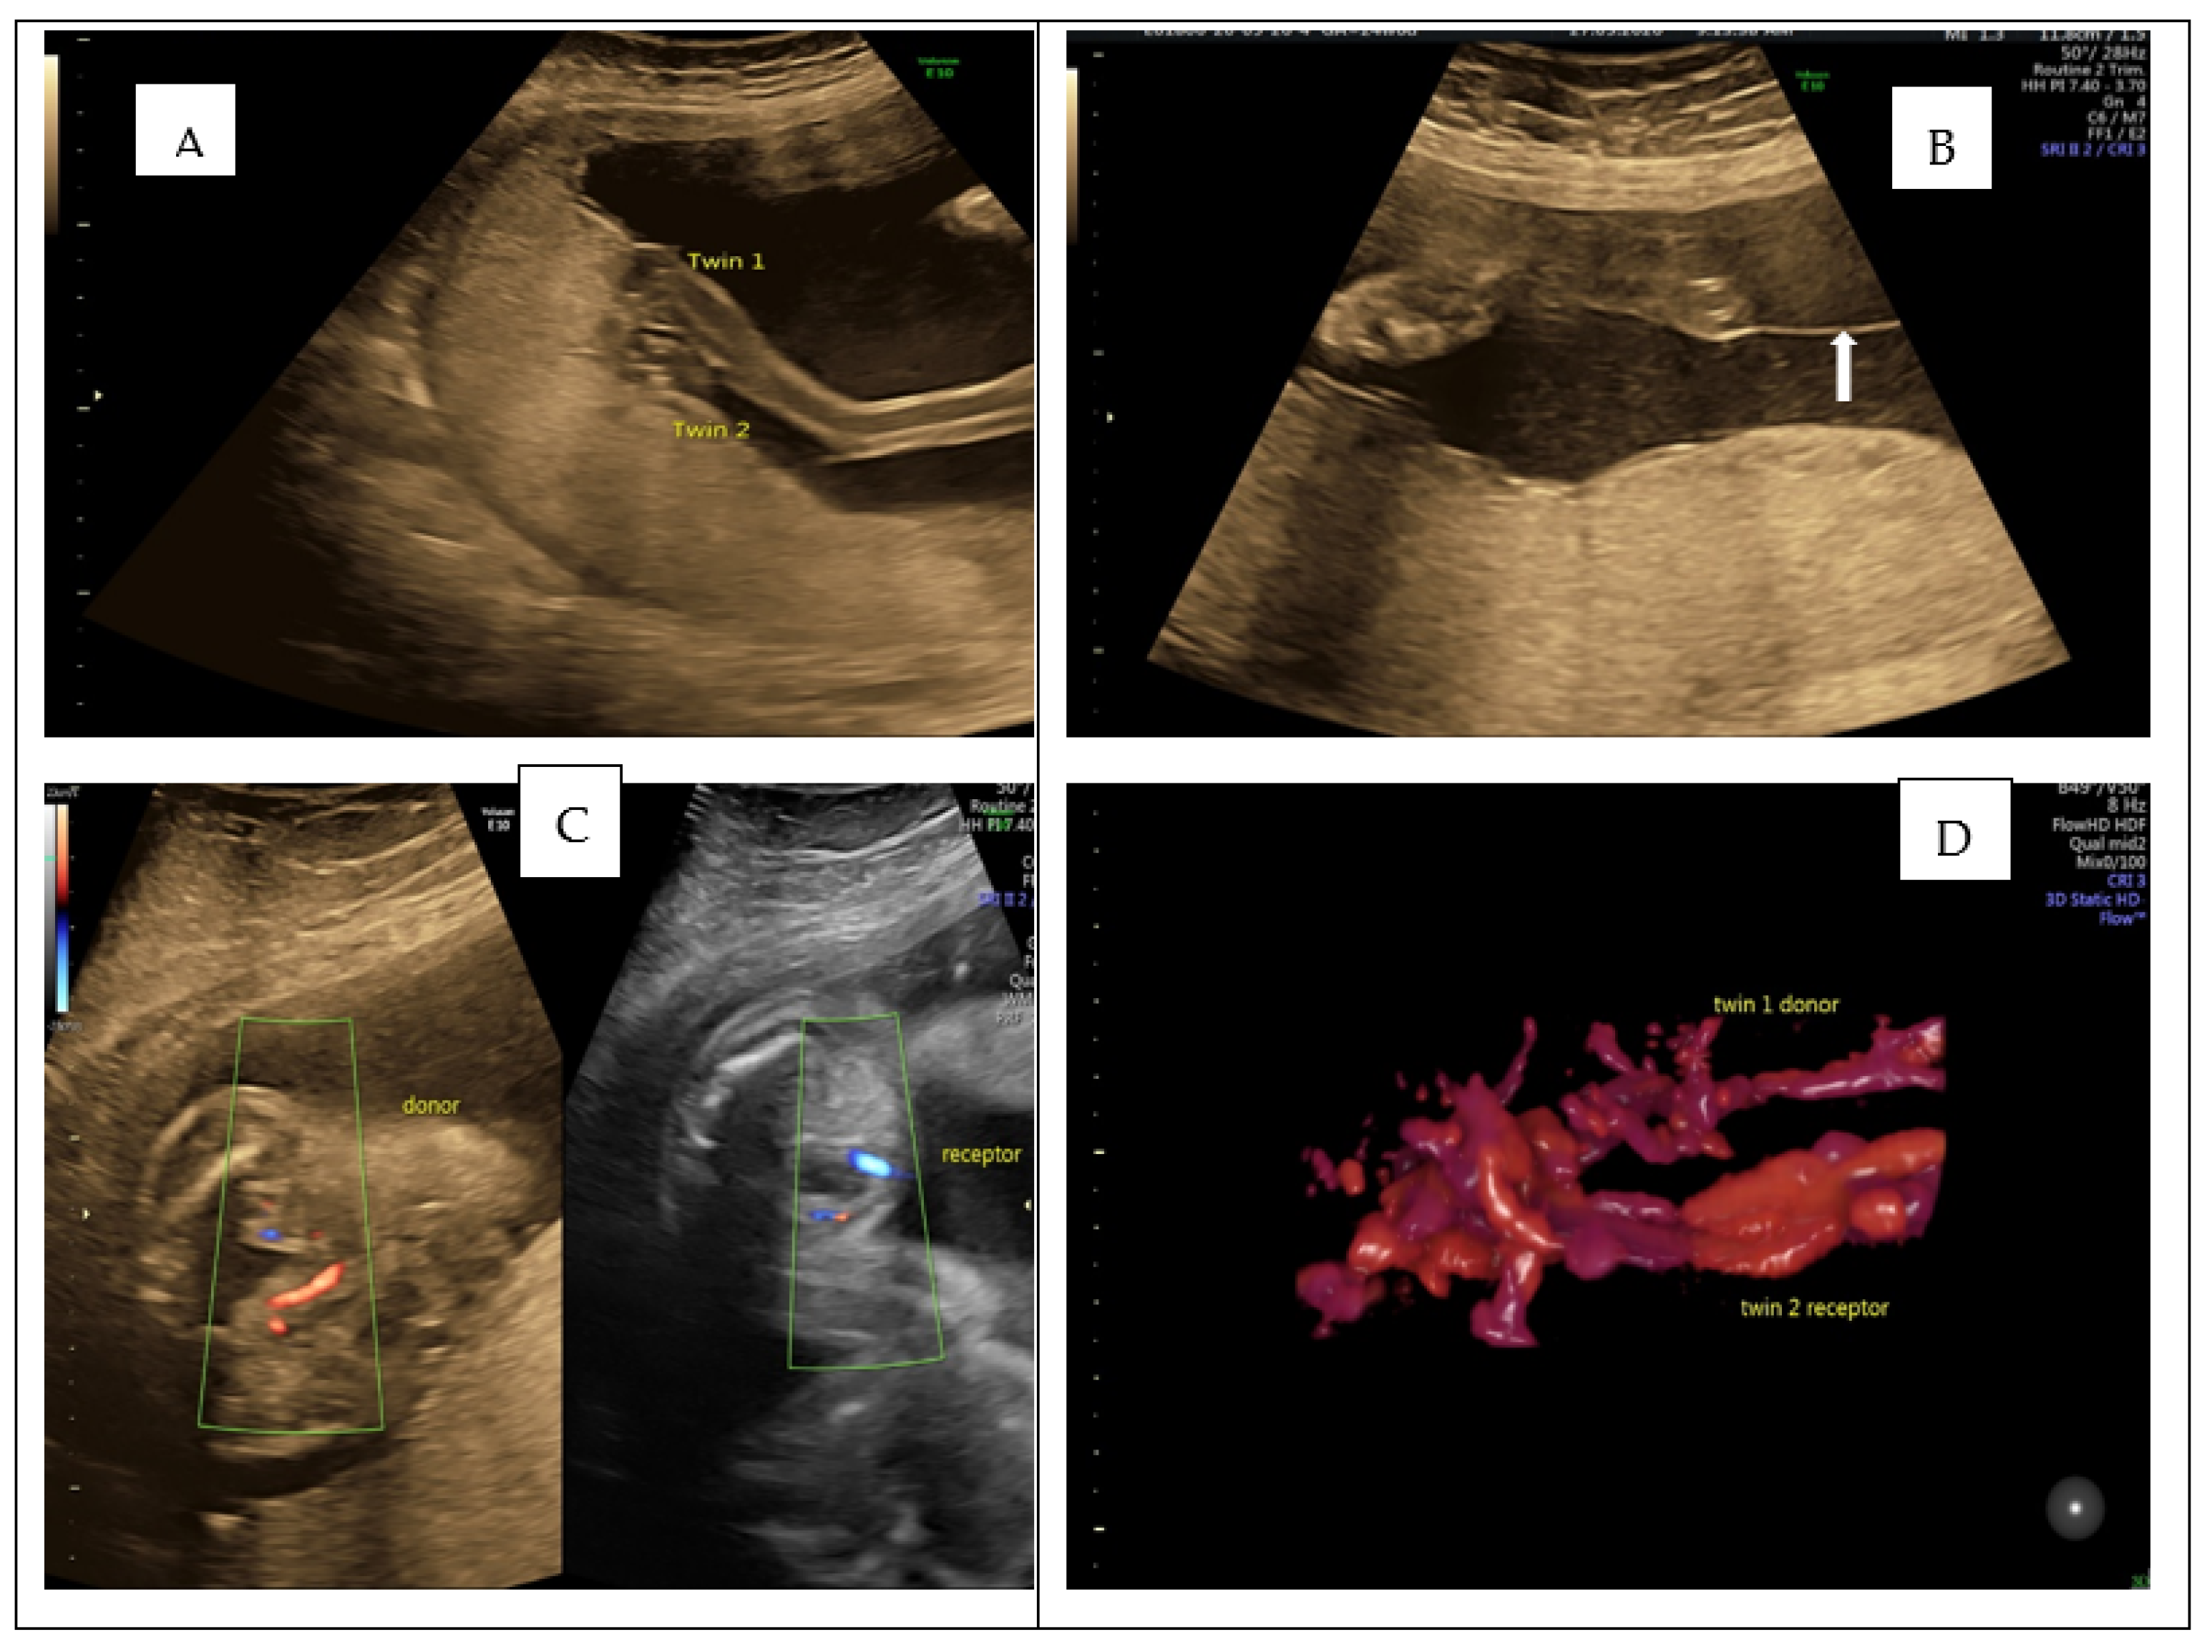

Monochorionic Diamniotic Twins with Bordering Cord Insertions: Images and Outcome